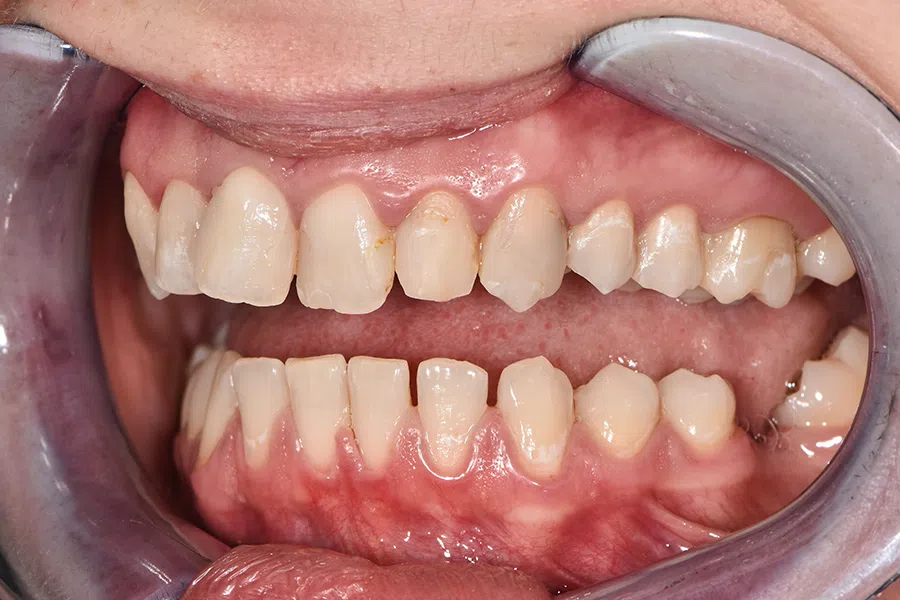

Înainte

Caz de estetică dentară – Fațete ceramică presată E-Max

Provocarea acestui caz a fost în prepararea minim invazivă a dinților centrali rotați și a obține o formă și o culoare cât mai naturală, pacienta dorind un caz de estetică dentară ce să nu fie observabil.

Pacienta a beneficiat de corecție gingivala cu laser pentru uniformizarea asimetriilor gingivale, tratamente endodontice de canal sub microscop, obturațiile vechi (plombe) schimbate cu materiale de compozit cu particule nanoceramice, și fațete dentare din ceramică presată E-Max.

Termen de finalizare 2 săptămâni de la amprentarea finală.